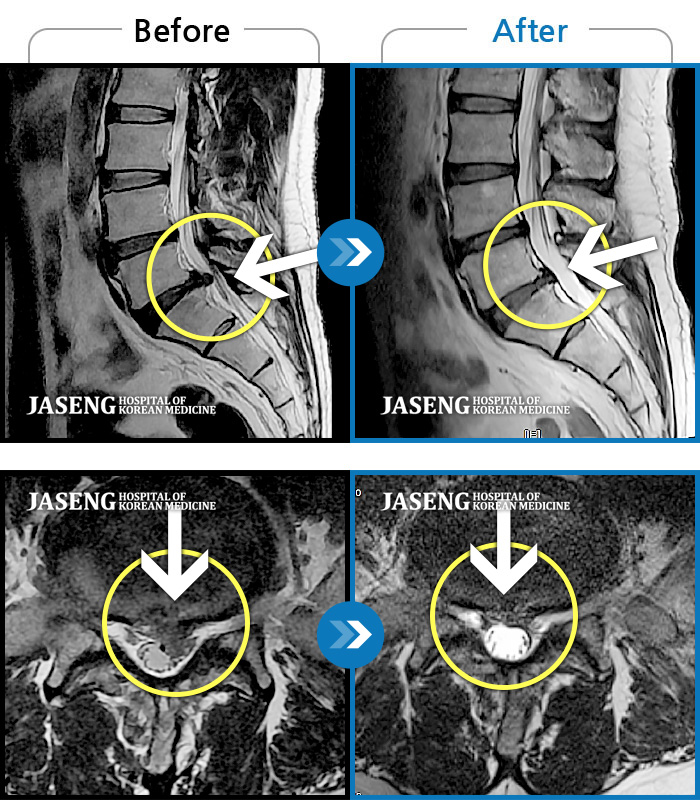

컴퓨터 모니터로 많이 튀어나온 디스크도 쑥 들어간 mri사진 사례들을 여러개 보여주시며 이보다 더 많은 사례가 있다고 제게 희망을 주셨습니다